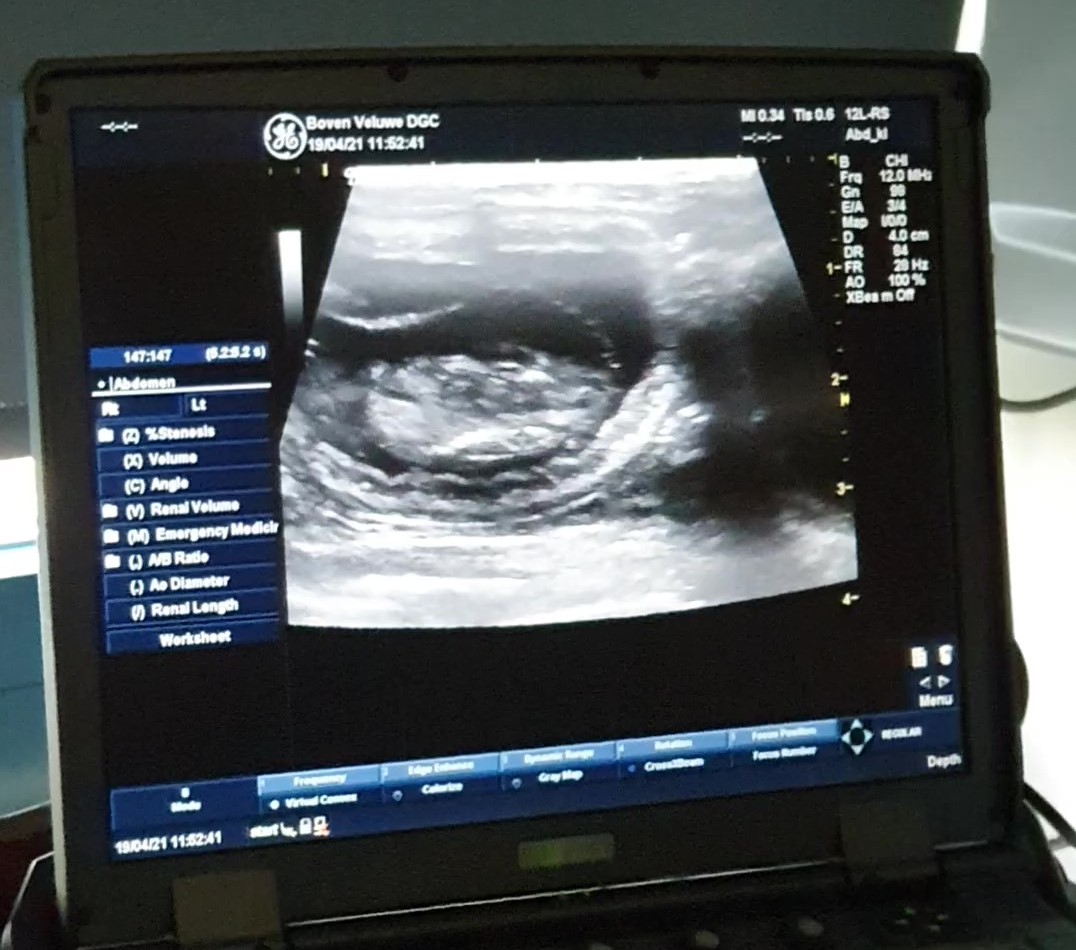

Zoals gezegd hebben we een deel van de echo gefilmt. U kunt hier klikken om naar het filmpje te gaan. Maar misschien is het beter om eerst naar de foto's te kijken en dan naar het filmpje, dan zijn sommige beelden misschien wat logischer. Er zit geluid bij het filmpje. De dierenarts zegt 2 maal wanneer je een hartje in beeld zit kloppen, maar je moet wel goed kijken hoor.Doordat Bubbles zo slank gebouwd is (ook omdat het nog een jonge poes is) hebben we wat leuke plaatjes. Deze zijn gemaakt met een echo apparaat dat uit een ziekenhuis komt. Eerst kijken we met de gewone echokop om de dracht te zien en een goed overzicht te krijgen. Daarna gaat de kop die voor baby's wordt gebruikt erop en zien we heel veel detail. De foto's hieronder zijn van de echo met die laatste kop gemaakt.

Dit is zo leuk, dat heb ik nog niet eerder gezien, dat er 2 kittens zo dicht bij elkaar liggen dat ze samen op 1 beeld te zien zijn hier zie je een rug aanzicht van een kitten met in het midden van links naar rechts de ruggengraat. nog een keer de 2 kittens in beeld gekomen en misschien ook een stukje van nummer 3 daar onder in het midden? Hier zie je weer een ruggengraat met recht het hoofdje, maar je ziet ook de ribjes links en rechts van de ruggengraat. Links zie je in het midden de navelstreng richting het kitten gaan. en nog een, gewoon omdat het leuk is. Het is net een honingraad daarbinnen met allemaal kittenkamertjes ;-) hier zie je er 4 maar het is bij een echo ook altijd de vraag of het allemaal verschillende zijn, de dierenarts denkt dat het er 5 zijn, we zullen het gaan zien bij de geboorte.